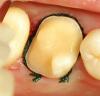

METT Опубликовано 13 апреля, 2013 Автор Поделиться Опубликовано 13 апреля, 2013 37 точево,вкладку еще не фотал Ссылка на комментарий

METT Опубликовано 13 апреля, 2013 Автор Поделиться Опубликовано 13 апреля, 2013 26 точево Ссылка на комментарий